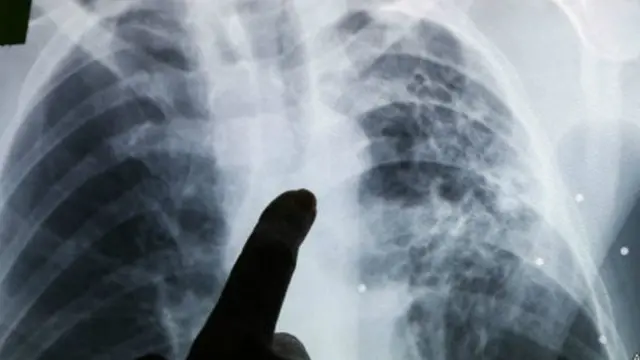

डॉक्टरों और पशु चिकित्सकों का कहना है कि जानवरों को होने वाली टीबी की बीमारी इंसानों के लिए काफ़ी ख़तरनाक हो सकती है हालांकि पहले इसे ज़्यादा बड़ा ख़तरा नहीं माना जाता था.

अगर इंसानों को इस तरह से टीबी की बीमारी हो जाए तो हालत ज़्यादा गंभीर हो सकती है और उसका इलाज भी टीबी की आम बीमारियों के मुक़ाबले ज़्यादा मुश्किल होगा.

डॉक्टर फ़्रांसिस्को ओलिया पोपेल्का के मुताबिक एक बार किसी को यह बीमारी हो जाए तो यह अक्सर फेफड़े के साथ ही दूसरे अंगों पर असर डालती है जिसकी वजह से बीमारी का बता लगाना मुश्किल हो जाता है और इसलिए इसका इलाज भी कठिन हो जाता है.